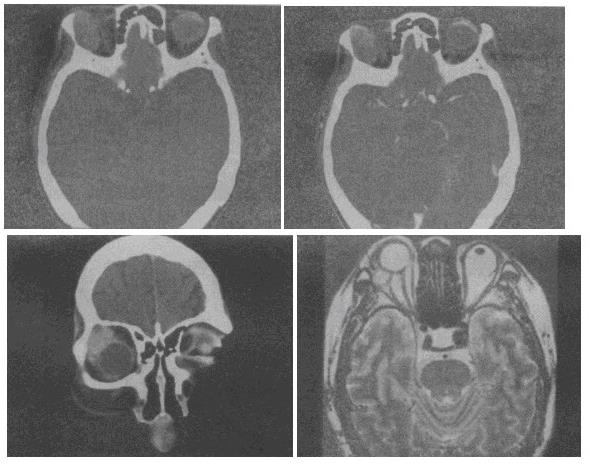

- 单项选择题 男,41岁,右侧眼眶外上方肿胀,可触及无痛性包块,CT及MRI检查如图,最可能的诊断是()。

D、泪腺混合瘤

- D